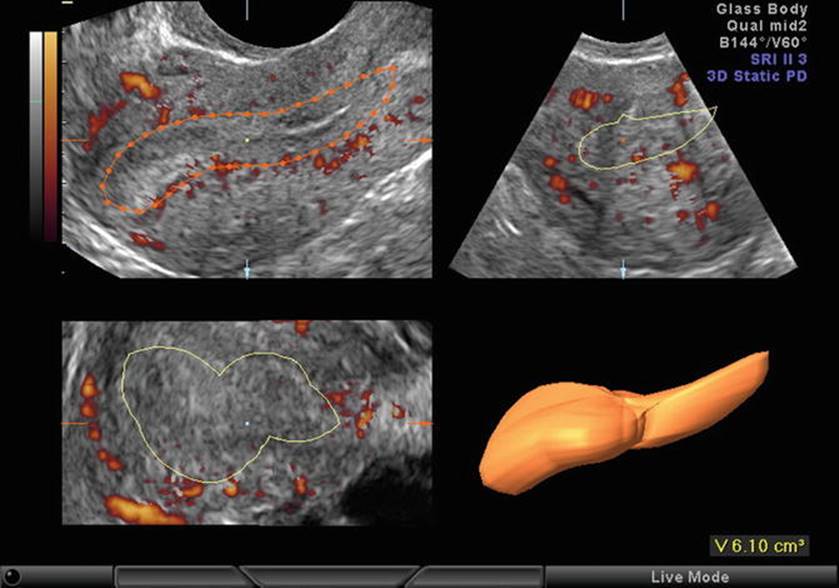

Fig. 2.3

(a, b) Stromal blood flow

Stromal Blood Flow (Fig. 2.3a, b)

· Stromal Flow Index (FI) [6]

· <11 low responder

· 11–14 Normal responders

· >15 risk of OHSS

· Stromal Peak Systolic Velocity (PSV)

· Low stromal PSV in the early follicular phase predicts poor responders

· Increased stromal PSV with unchanged resistance predicts increased risk of OHSS